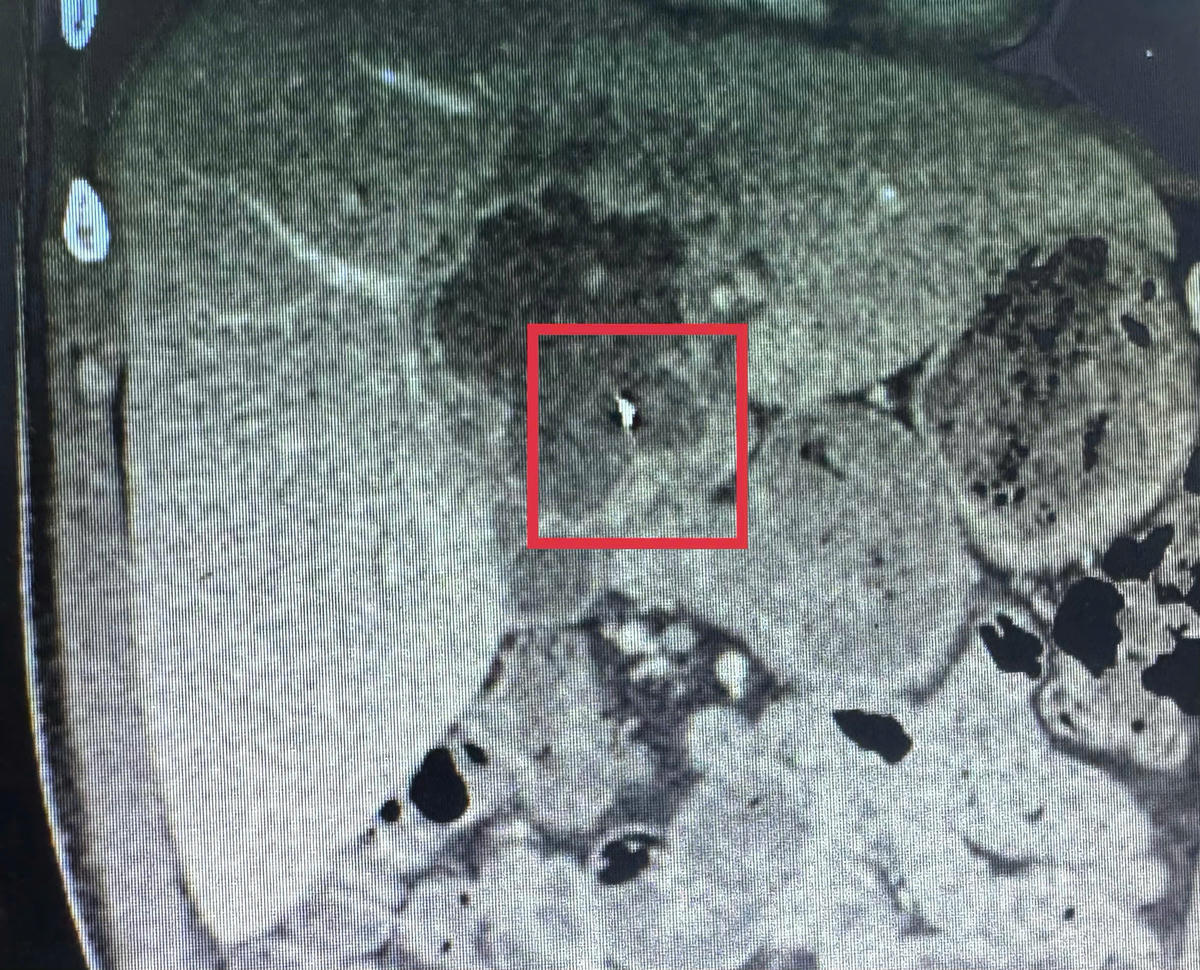

Trước đó, ngày 9/2, bệnh nhân T.T.L (41 tuổi, ngụ xã Nhơn Phú, tỉnh Vĩnh Long) nhập viện trong tình trạng đau dữ dội vùng thượng vị kèm sốt cao. Qua thăm khám lâm sàng, kết hợp siêu âm ổ bụng và chụp CT-scan, các bác sĩ phát hiện ổ áp xe gan kích thước khoảng 5x6 cm, bên trong có dị vật kim loại dài khoảng 6 cm, tình huống hiếm gặp.

Ca phẫu thuật do ê-kíp Ngoại Tổng quát thực hiện, với ThS.BS.CKI Trần Nhật Phi là phẫu thuật viên chính. Sau gần 60 phút phẫu thuật, ê-kíp đã lấy thành công dị vật là kim may quần áo dài khoảng 6 cm, đồng thời dẫn lưu khoảng 200 ml mủ đục trong ổ áp xe. Phương pháp nội soi giúp hạn chế xâm lấn, giảm đau sau mổ và rút ngắn thời gian hồi phục cho người bệnh.

Theo ThS.BS.CKI Trần Nhật Phi, khó khăn của ca bệnh là ổ áp xe nằm sâu trong nhu mô gan, dị vật ở vị trí gần các mạch máu lớn nên việc tiếp cận và xử lý đòi hỏi sự thận trọng cao để bảo đảm an toàn và xử lý triệt để ổ nhiễm trùng.